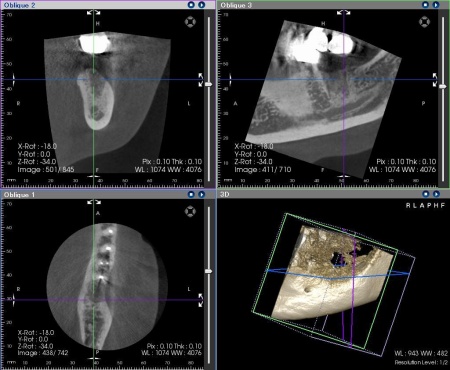

その後、歯科用CT撮影を行い、顎の骨の量や形、神経や血管の位置を立体的に確認しました。撮影したデータをもとに、インプラントを埋め込む位置や角度、深さについて事前に設計を行い、安全性と噛み合わせのバランスを考慮した治療計画を立てます。

インプラントの埋入設計をしました。